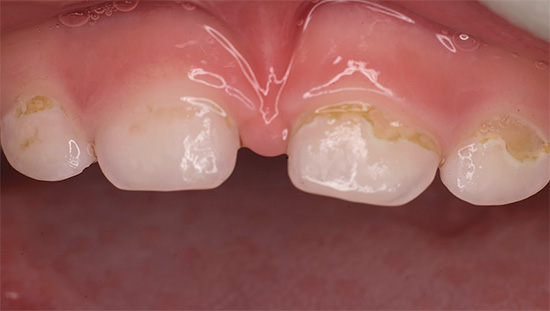

Nelle prime fasi, la carie di bottiglia può manifestarsi sotto forma di punti chiari opachi (stadio di una macchia bianca o di gesso), che nel tempo assumono la forma di rugosità sullo smalto, gradualmente si approfondiscono e si scuriscono.

Nella fase di una macchia bianca o debolmente pigmentata, è spesso possibile ripristinare quasi completamente l'area dello smalto danneggiata utilizzando metodi di terapia rimineralizzante. A casa, i denti vengono regolarmente trattati con gel speciali come R.O.C.S. Medical Minerals o GC Tooth Mousse. Ma non si può decidere il trattamento da soli con il loro aiuto: solo il medico dovrebbe determinare lo stadio di sviluppo della carie e prescrivere un trattamento.